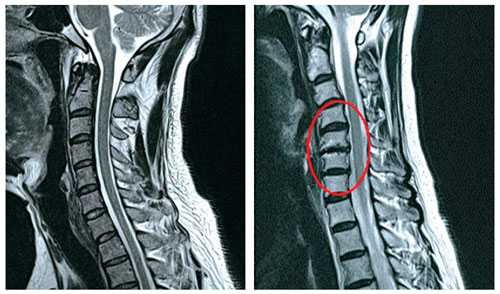

목 뼈와 뼈 사이의 디스크가 제자리에서 이탈되어 신경을 압박하던가 뼈 조직이 비정상적으로 자라 목을 지나는 척추 신경이 눌려 통증을 인지하는 질환이고요.

디스크의 수핵이 빠져나가거나 퇴행성 경추 척추증 및 경추관협착증 등으로 척수가 눌리게 되면 거의는 팔의 힘이 빠지는 느낌을 받을 수 있습니다.

목 디스크 증상으로 저림 현상을 겪으실 수 있다고 합니다. 이유는 디스크의 수핵이 빠져나가거나 퇴행성 경추 척추증등으로 척수가 눌리게 되는 만큼 팔의 힘이 빠지고 저린 경우가 많으므로져요. 척수가 눌린 강도에 따라서는 팔이 마비가 되기도 하며, 어지럼증을 또한 맛볼 수도 있어요.